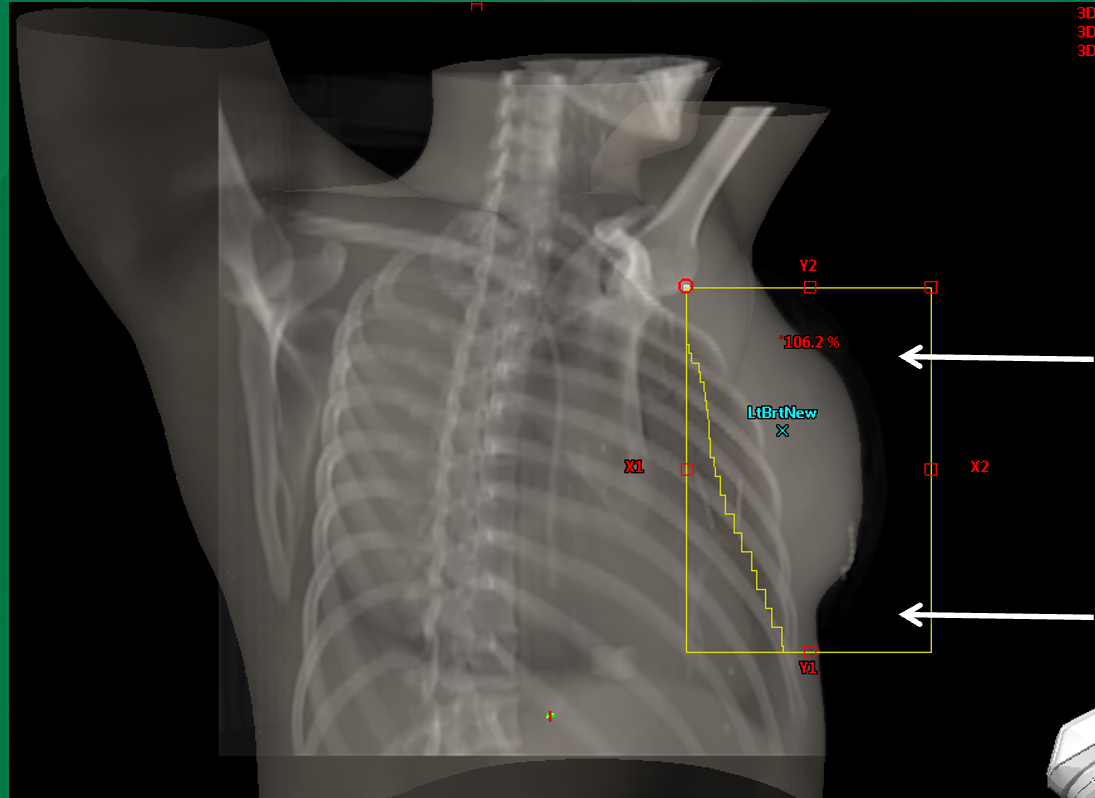

How does FLASH irradiation in air affect central axis dose calculations?

It alters the central axis conditions because part of the beam travels through air instead of tissue. 1D calculations assume tissue along the central axis, but in reality there may be air.

How does TPS (e.g., Eclipse Treatment Planning System) handle FLASH scenarios better than 1D calculations?

It accounts for heterogeneities like air vs tissue in its 3D dose calculation. 1D calculations do not accurately account for changes in scatter and attenuation